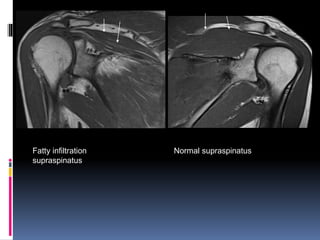

 Complete tears of supraspinatus tendon are

accompanied by muscle atrophy and fatty

infiltration.

 These are important negative prognostic

factors for tendon repair and shoulder

arthroplasty.

 Muscle thickness using Fat occupancy ratio

and fatty infiltration of muscle can be

assessed on MRI.

Fatty infiltration

supraspinatus

Normal supraspinatus